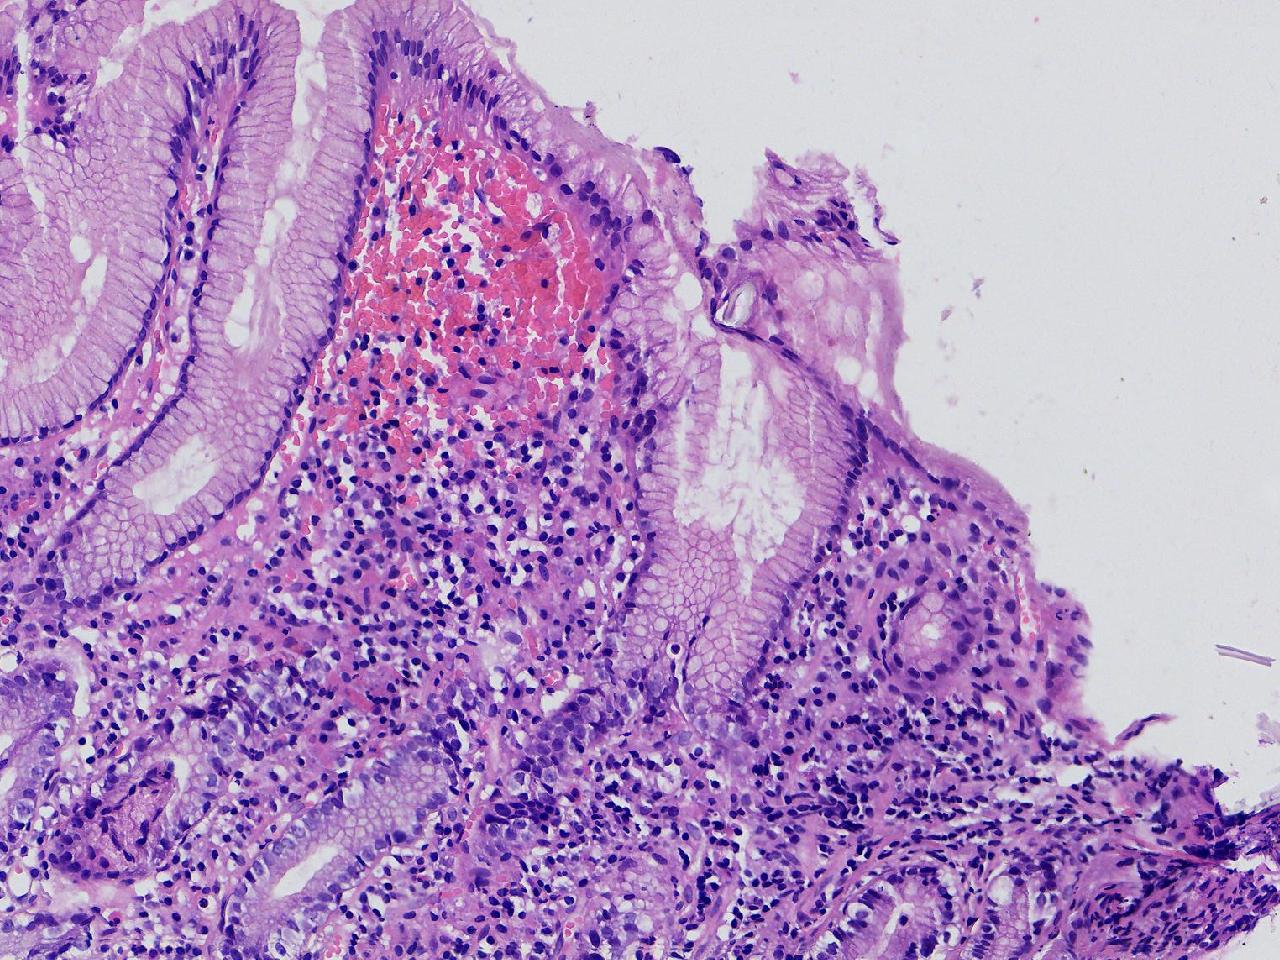

间质内是炎细胞吗?

男,49岁,胃镜活检,胃窦粘膜红白相间,以红为主,后壁见一直径约0.4cm大小片平隆起,表面糜烂,活检1块送检,质软弹性可。

胃窦活检

灰白色不整形软组织1块,直径0.2厘米。

是!还有组织细胞

幽门型粘膜中度慢性炎

是的,主要是淋巴细胞和浆细胞。